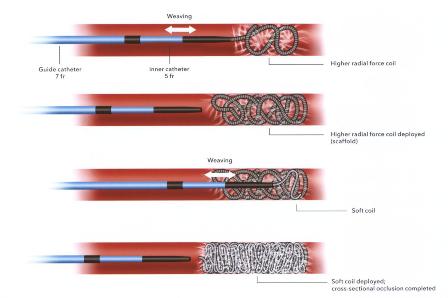

技术之二,锚定和脚手架技术:主要用于大动脉阻塞,将弹簧栓子部分锚定在血管的某一分支上。弹簧栓子的直径>血管直径。往复推送弹簧栓子(go to and fro and push)

anchor scaffolding 技术

|

|

可推送弹簧栓子的锚定(Anchor)技术,可以避免释放后移位,或增加截面积的填塞。如果第一个弹簧栓子被锚定,就无需担心其是否会稳定 |

脚手架技术(Scaffold technique)

|

|

选用较大的弹簧栓子,利用高径向支撑力。可推式弹簧栓子的脚手架(Scaffold)技术。先非致密性阻塞血管,再将推送管重新推回起始点在释放弹簧栓子。 |